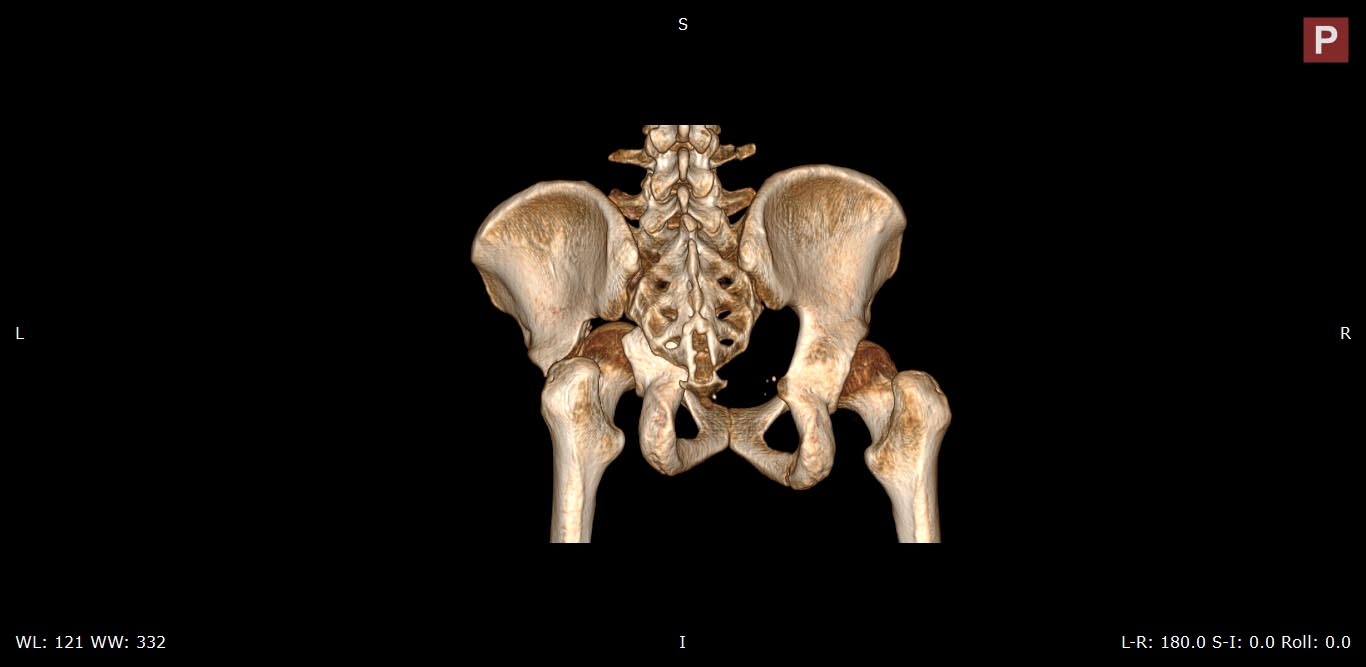

Это поперечный перелом вертлужной впадины, а не перелом таза.

И справа похоже тоже вертлужка сломанна .

Да, справа без смещения

Добрый день, уважаемые коллеги! Данный случай-полифокальное повреждение таза.Самый неблагоприятный вариант поперечно ориентированного перелома вертлужной впадины и ротационно нестабильное повреждение тазового кольца (КПС). Оперативное лечение- открытая реконструкция сустава и перкутанная фиксация КПС.

Вчера (17.10.17) снимок на месте палатным аппаратом.

Положение отломков прежнее.

Кт в день поступления прилагаю.